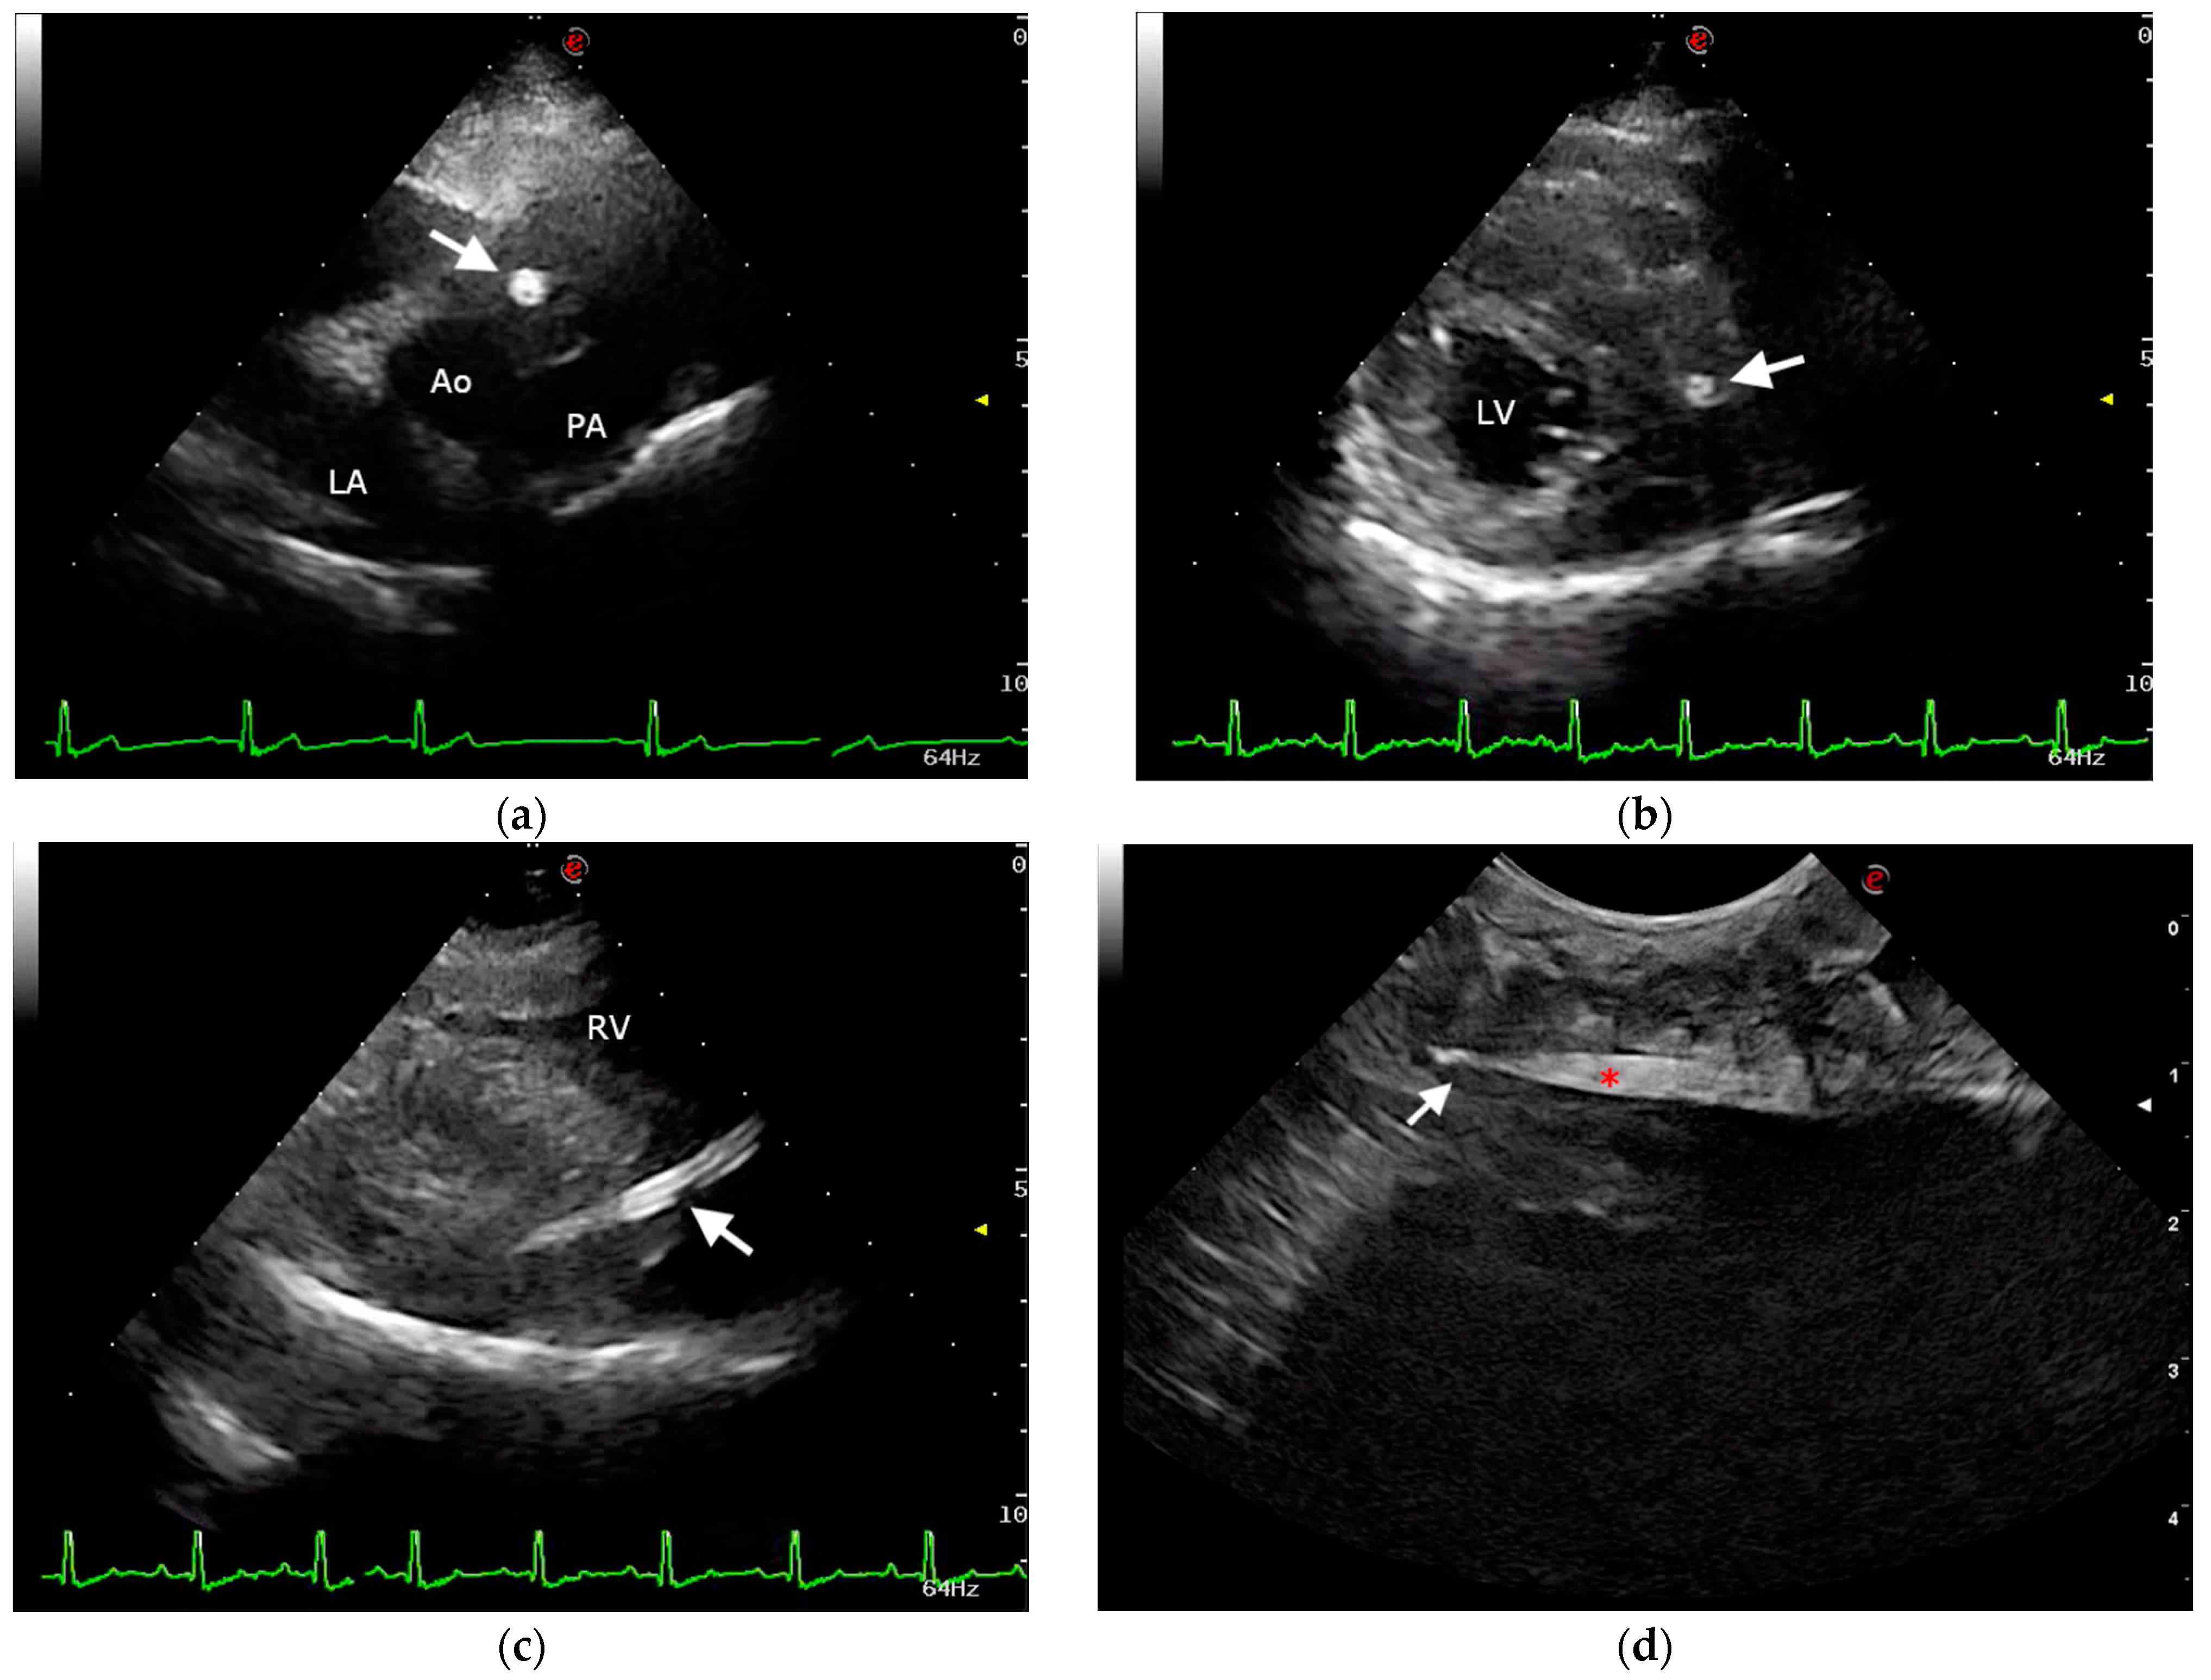

2.1. Case Description and Clinical Investigations